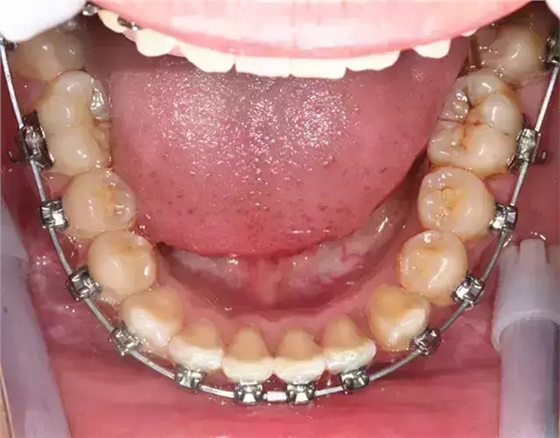

患者側(cè)面凸,鼻唇角較銳,笑時(shí)露齦笑明顯上下牙列擁擠,磨牙尖牙Ⅱ 類關(guān)系,3 度的深覆牙合,上頜中切牙伸長內(nèi)傾拔除上頜雙側(cè)的第一前磨牙,先粘上頜高轉(zhuǎn)矩的自鎖托槽排齊牙列,唇向開展上頜切牙,有一定的覆蓋,粘下頜標(biāo)準(zhǔn)轉(zhuǎn)矩托槽,上頜 1, 2 之間植入種植支抗壓入,同時(shí)后牙 5, 6 之間植入種植支抗內(nèi)收前牙,打開咬合關(guān)閉間隙。治療關(guān)鍵:前牙轉(zhuǎn)矩的控制第 1 個(gè)月 上頜粘上 Damon Q 高轉(zhuǎn)矩托槽,上 .014 熱激活 NiTi 絲。第 3 個(gè)月 上換 .014 x .025 熱激活 NiTi 絲。第 5 個(gè)月 上頜基本排齊,覆蓋增大,上換 .017 x .025 NiTi絲,下頜粘托槽,下 .014 熱激活 NiTi 絲。第 7 個(gè)月 上 .017 x .025 NiTi 絲加搖椅,下?lián)Q .014 x .025 熱激活 NiTi 絲第 9 個(gè)月 上頜換 .019 x .025 NiTi 絲加搖椅,下頜換 .017 x .025 NiTi 絲第 11 個(gè)月 下頜換 .019 x .025 加搖椅,上頜 1, 2 之間, 5, 6 之間植入種植釘,下頜出現(xiàn)散隙。第 13 個(gè)月 上頜換 .019 x .025ss 加搖椅,前牙種植釘用 Power Chain 壓低前牙(每側(cè) 100g),后牙種植釘關(guān)閉間隙(每側(cè) 150g),下?lián)Q .019 x .025ss,Power Chain 關(guān)閉間隙。第 19 個(gè)月 上頜前牙基本壓低到位去除前牙種植釘,繼續(xù)用關(guān)閉間隙,下頜散隙關(guān)閉。